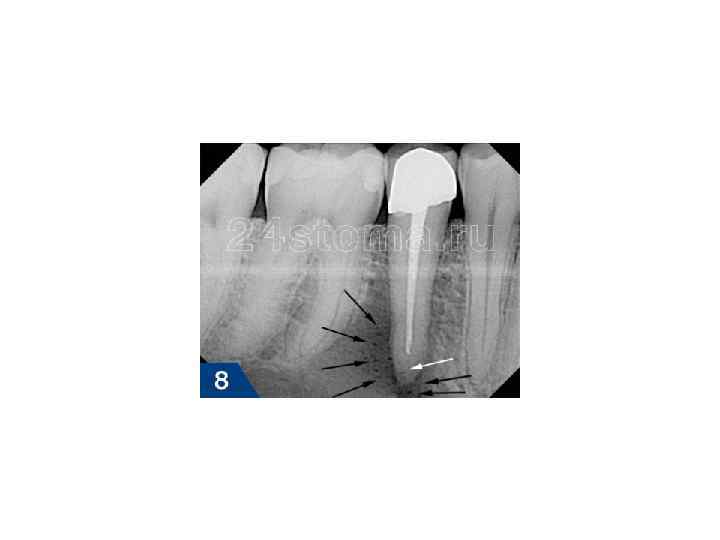

Диагностика хронического периодонтита • основывается на клинической картине и рентгенологических данных. На рентгенограмме при гранулирующем периодонтите обнаруживаются типичные изменения — очаг разрежения костной ткани в области верхушки корня. Линия периодонта в этом отделе не видна из -за инфильтрирующего роста грануляционной ткани, приводящего к рассасыванию стенок лунки, а также цемента и дентина корня. Поверхности их становятся неровными. Эту неровность выявляют более отчетливо со стороны костной ткани, в которую из периодонта идут небольшие выросты

Диагностика • основывается на клинической картине, но чаще всего на рентгенологических данных. На рентгенограмме при гранулематозном периодонтите в околоверхушечной области виден округлый очаг разрежения костной ткани с четкими ровными границами. При правильно проведенном консервативном лечении на месте гранулематозного очага выявляют изменения, характерные для фиброзного периодонтита, или образование участка склерозированной костной ткани

Диагностика • основывается на данных рентгенографии. На рентгенограмме выявляют расширение линии периодонта, главным образом у верхушки корня зуба. Иногда в результате гиперцементоза обнаруживают значительное утолщение верхушечного участка корня. Костная пластинка, ограничивающая расширенную линию периодонта, нередко утолщена, склерозирована